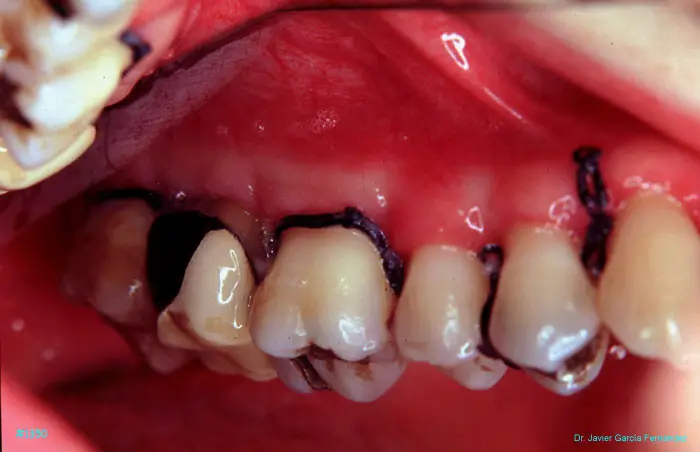

Atlas of Surgical Techniques in Periodontics. Chapter III. Atlas de Técnicas Quirúrgicas en Periodoncia